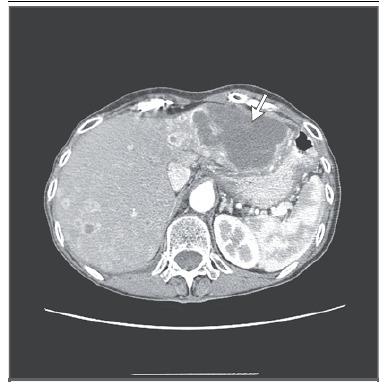

对于另外 75% 的患者,免疫组化结果不能明确其诊断。图 4 显肝脏巨大肿块,影像学提示胆管癌。

图 4 原发灶不明的转移癌与胆管癌的鉴别。由于原发灶不明的转移癌中肝脏受累很常见,与胆道肿瘤的鉴别则显得尤为重要,尤其伴或不伴卫星结节,有大的孤立肝脏肿块的患者。MRI 多相扫描显示延长期强化, 提示胆管癌(箭头处)。免疫组化检测没有诊断价值,应避免做多种分子印迹检测。

这些病例的免疫组化结果往往是非特异性的,而胆管癌通常不认为是原发灶不明的转移癌。免疫组化检测结果非特异性的患者可根据临床病理选择以铂类为基础的方案,也可采取包括组织来源分子分析和新一代测序在内的基因组学研究。许多肿瘤缺乏具体而有效的药物,而且大多数肿瘤的治疗方案也有重叠。然而,随着普通已知肿瘤新的治疗方法的研发,分子诊断工具可能成为原发灶不明的转移癌的基石。